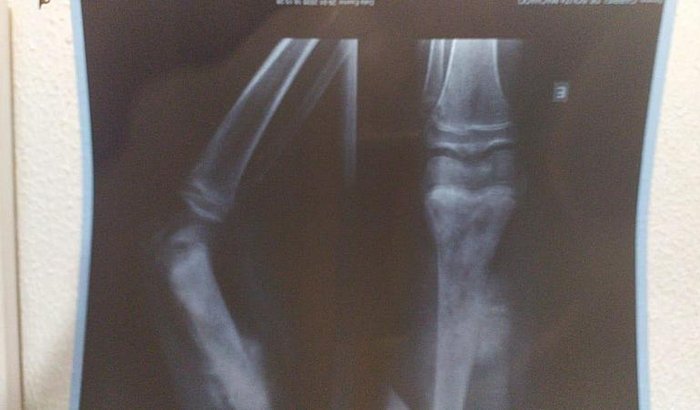

Gabriel De Souza Machado Tem 11 Anos E Devido A Dor E Inchaço Na Perna No Dia 29/01/2020 Fez Um Raio-X Que Detectou Um Tumor Na Perna Esquerda Com 17cm. Outros Exames Foram Feitos E Dia 03/02/2020 Infelizmente Foi Confirmado Um Câncer. Mais Exames Estão Sendo Feitos E Tomografia,Cintilografia, Biópsia. Porém Esses Exames Estão Sendo Feitos Em Minas Gerais Onde Será Dado Inicio Ao Tratamento. Nesse Momento Além Dos Gastos Com Os Primeiros Exames Estamos Tendo Muitos Gastos Com Transporte, Hospedagem E Alimentação. Agradecemos A Todos Que Puderem Ajudar, Não Só Com As Doações Mas Também Orações E Compartilhamento Para Alcançarmos Mais Pessoas

Gabriel De Souza Machado is 11 years old and due to pain and swelling in his leg on 29/01/2020 he underwent an X-ray that detected a 17cm left leg tumor. Other exams were done and on 03/02/2020 Unfortunately a cancer was confirmed. More Exams Are Being Taken And Tomography, Scintigraphy, Biopsy. However, these exams are being done in Minas Gerais where treatment will begin. At this moment, in addition to the expenses with the first exams, we are having many expenses with transportation, accommodation and food. We thank everyone who can help, not only with donations but also prayers and sharing to reach more people